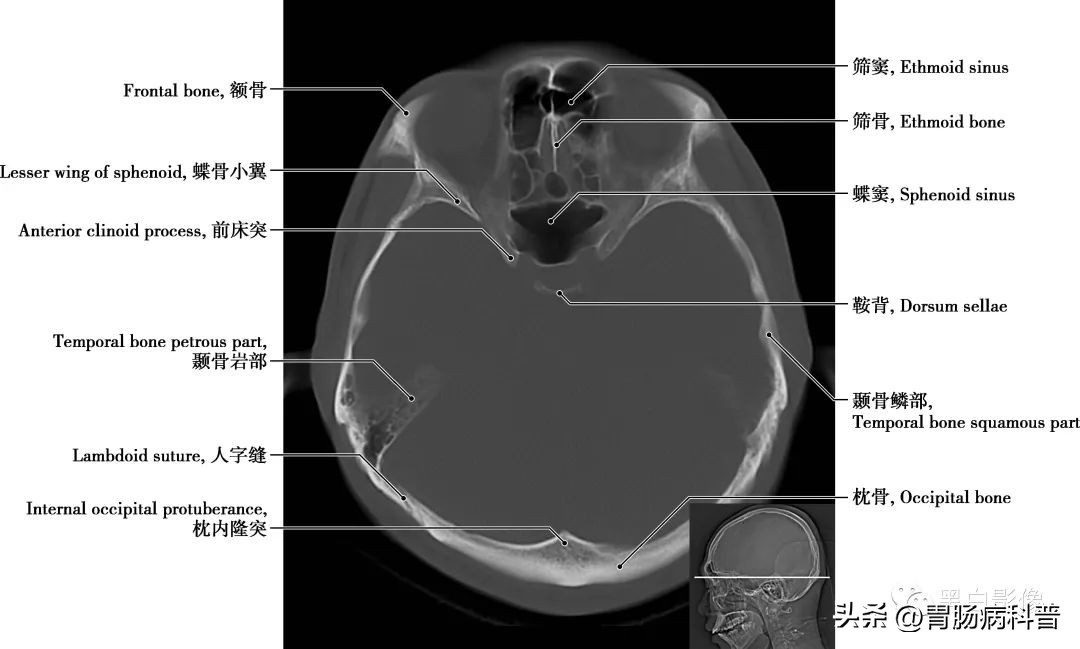

图1-2-11 经大脑脚轴位切面

眶顶 即眶上壁,前部为额骨水平板,后部为蝶骨小翼。鸡冠 筛板的前份向上伸出的骨嵴

图1-2-12 经脑桥轴位切面

筛窦 筛骨迷路内蜂窝状小房的总称,前、中筛窦开口于中鼻道,后筛窦开口于上鼻道。蝶骨小翼 从蝶骨体部前上方向左右平伸,小翼后缘是颅前窝和颅中窝的分界线,其根部有视神经管通过,两视神经管内口之间有视交叉沟联系。蝶窦 位于蝶骨体内,中间以薄骨板分隔成左、右两腔,分别向前开口于蝶筛隐窝。蝶窦上壁与垂体和视交叉等相邻